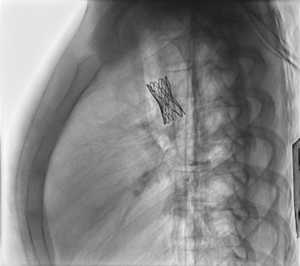

Zwężenie cieśni aorty u 15-letniej dziewczynki; A – aortografia, B – rekonstrukcja trójwymiarowa na podstawie aortografii rotacyjnej, C ? stan po implantacji stentu w miejscu zwężenia cieśni aorty.

Noworodek z zarośnięciem zastawki płucnej bez ubytku przegrody międzykomorowej i hipoplazją prawej komory serca;

A – pomiary średnicy przewodu tętniczego w aortografii;

B – stan po implantacji stentu do przewodu tętniczego.